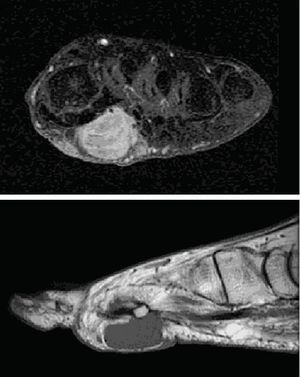

CaseA 53 year woman, without notable history, came to the emergency room presenting mechanical, intense pelvic pain and inability to stand or walk. Urgent laboratory analysis highlighted an alkaline phosphatase value of 398U/l (30–120), the rest of the blood count and biochemistry values were normal. AN AP radiograph of the pelvis showed osteopenia with no other findings. The patient was admitted and a second set of laboratory tests requested: phosphate 1.2mg/dl (2.5–4.5), alkaline phosphatase 395U/l (30–120), 1.25 vitamin D3 32.7ng/ml (30–40), phosphaturia, 1436.00mg/24h (400–1300). Other values were normal. An isotope bone scan was requested (Fig. 1), as were a pelvic CT (Fig. 2) and a pelvic MRI. A subsequent physical examination demonstrated that the patient had hard, painless, 2cm×2cm erythematous and bullous lesions on the sole of her left foot. Suspecting a phosphaturic tumor an octreotide scintigraphy was requested and found normal. We requested an MRI of the foot (Fig. 3) and removed the lesion. The pathologic diagnosis was: mixed connective tissue variant mesenchymal tumor. After removal of the tumor, the patient returned to normal blood and urine phosphate values and no new fractures occur.